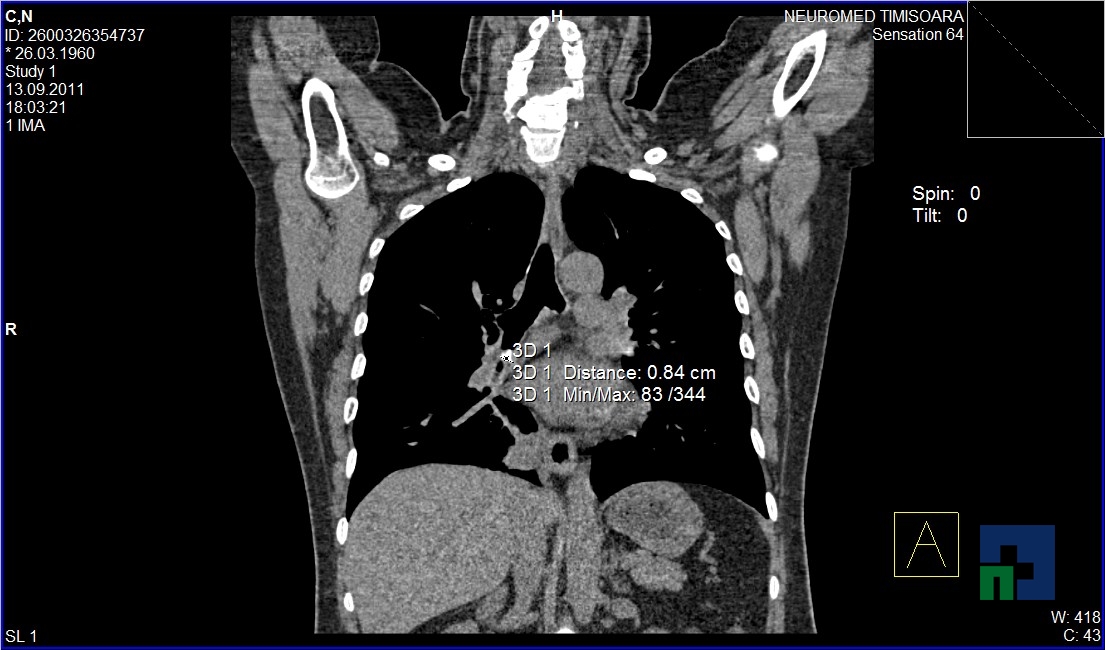

- Accidentelor vasculare cerebrale ischemice sau hemoragice

- Tumorilor cerebrale

- Tumorilor cerebrale: